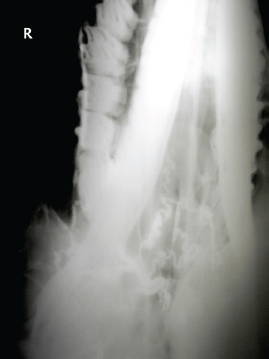

The left jugular vein appeared as an anechoic tubular structure which collapsed under the probe pressure, the color Doppler examination revealed normal blood flow within the vessel (Fig. 3). Bi-dimensional ultrasonography of the right jugular vein showed a heterogeneous, non-cavitating, hypoechoic structure occluding a narrowed right jugular vein for about 30 cm of length localized in the proximal and mid-portion of the neck compatible with a thrombus (Fig. 4). The color Doppler examination showed blood flow through the lateral portions of the thrombus in the cranial and mid-portions of the right jugular vein (Fig. 5). Cranially to the thrombus, a marked distension of the maxillary and linguofacial veins was evident, with a turbulent and echogenic flow; the latter was compatible with blood stasis near the thrombus (Fig. 6). Caudally to the thrombus, the right jugular vein presented reduced diameter, thickened walls, and normal blood flow (Fig. 7). The cranial part of the thrombus originated from a heterogeneous scare tissue, localized at the level of the right mandibular angle (Fig. 8). After injection of the first saline contrast bolus in a right facial vein, no microbubbles appeared in the right jugular vein, caudally to the thrombus, proving the presence of a complete right jugular vein occlusion. On the contrary, after injection of the second bolus, microbubbles were visualized in the left jugular vein as small, intense, echo signals within the vein lumen, demonstrating the presence of collateral circulation that drained the blood from the right facial veins to the left jugular vein (Fig. 9). Venography results confirmed the complete occlusion of the right jugular vein and the presence of submandibular venous collaterals that connected the right facial veins with the left jugular vein (Figs. 10 and 11). Based on the previous results, the diagnosis of JVT with complete occlusion of the vessel lumen was confirmed. The horse’s owner refused any proposed medical or surgical therapy.

Fig. 10. Venographic examination, latero-lateral view. Note the large number of collateral vessels draining the contrast.

Fig. 11. Venographic examination, ventro-dorsal view. Note the large number of collateral vessels draining the contrast.